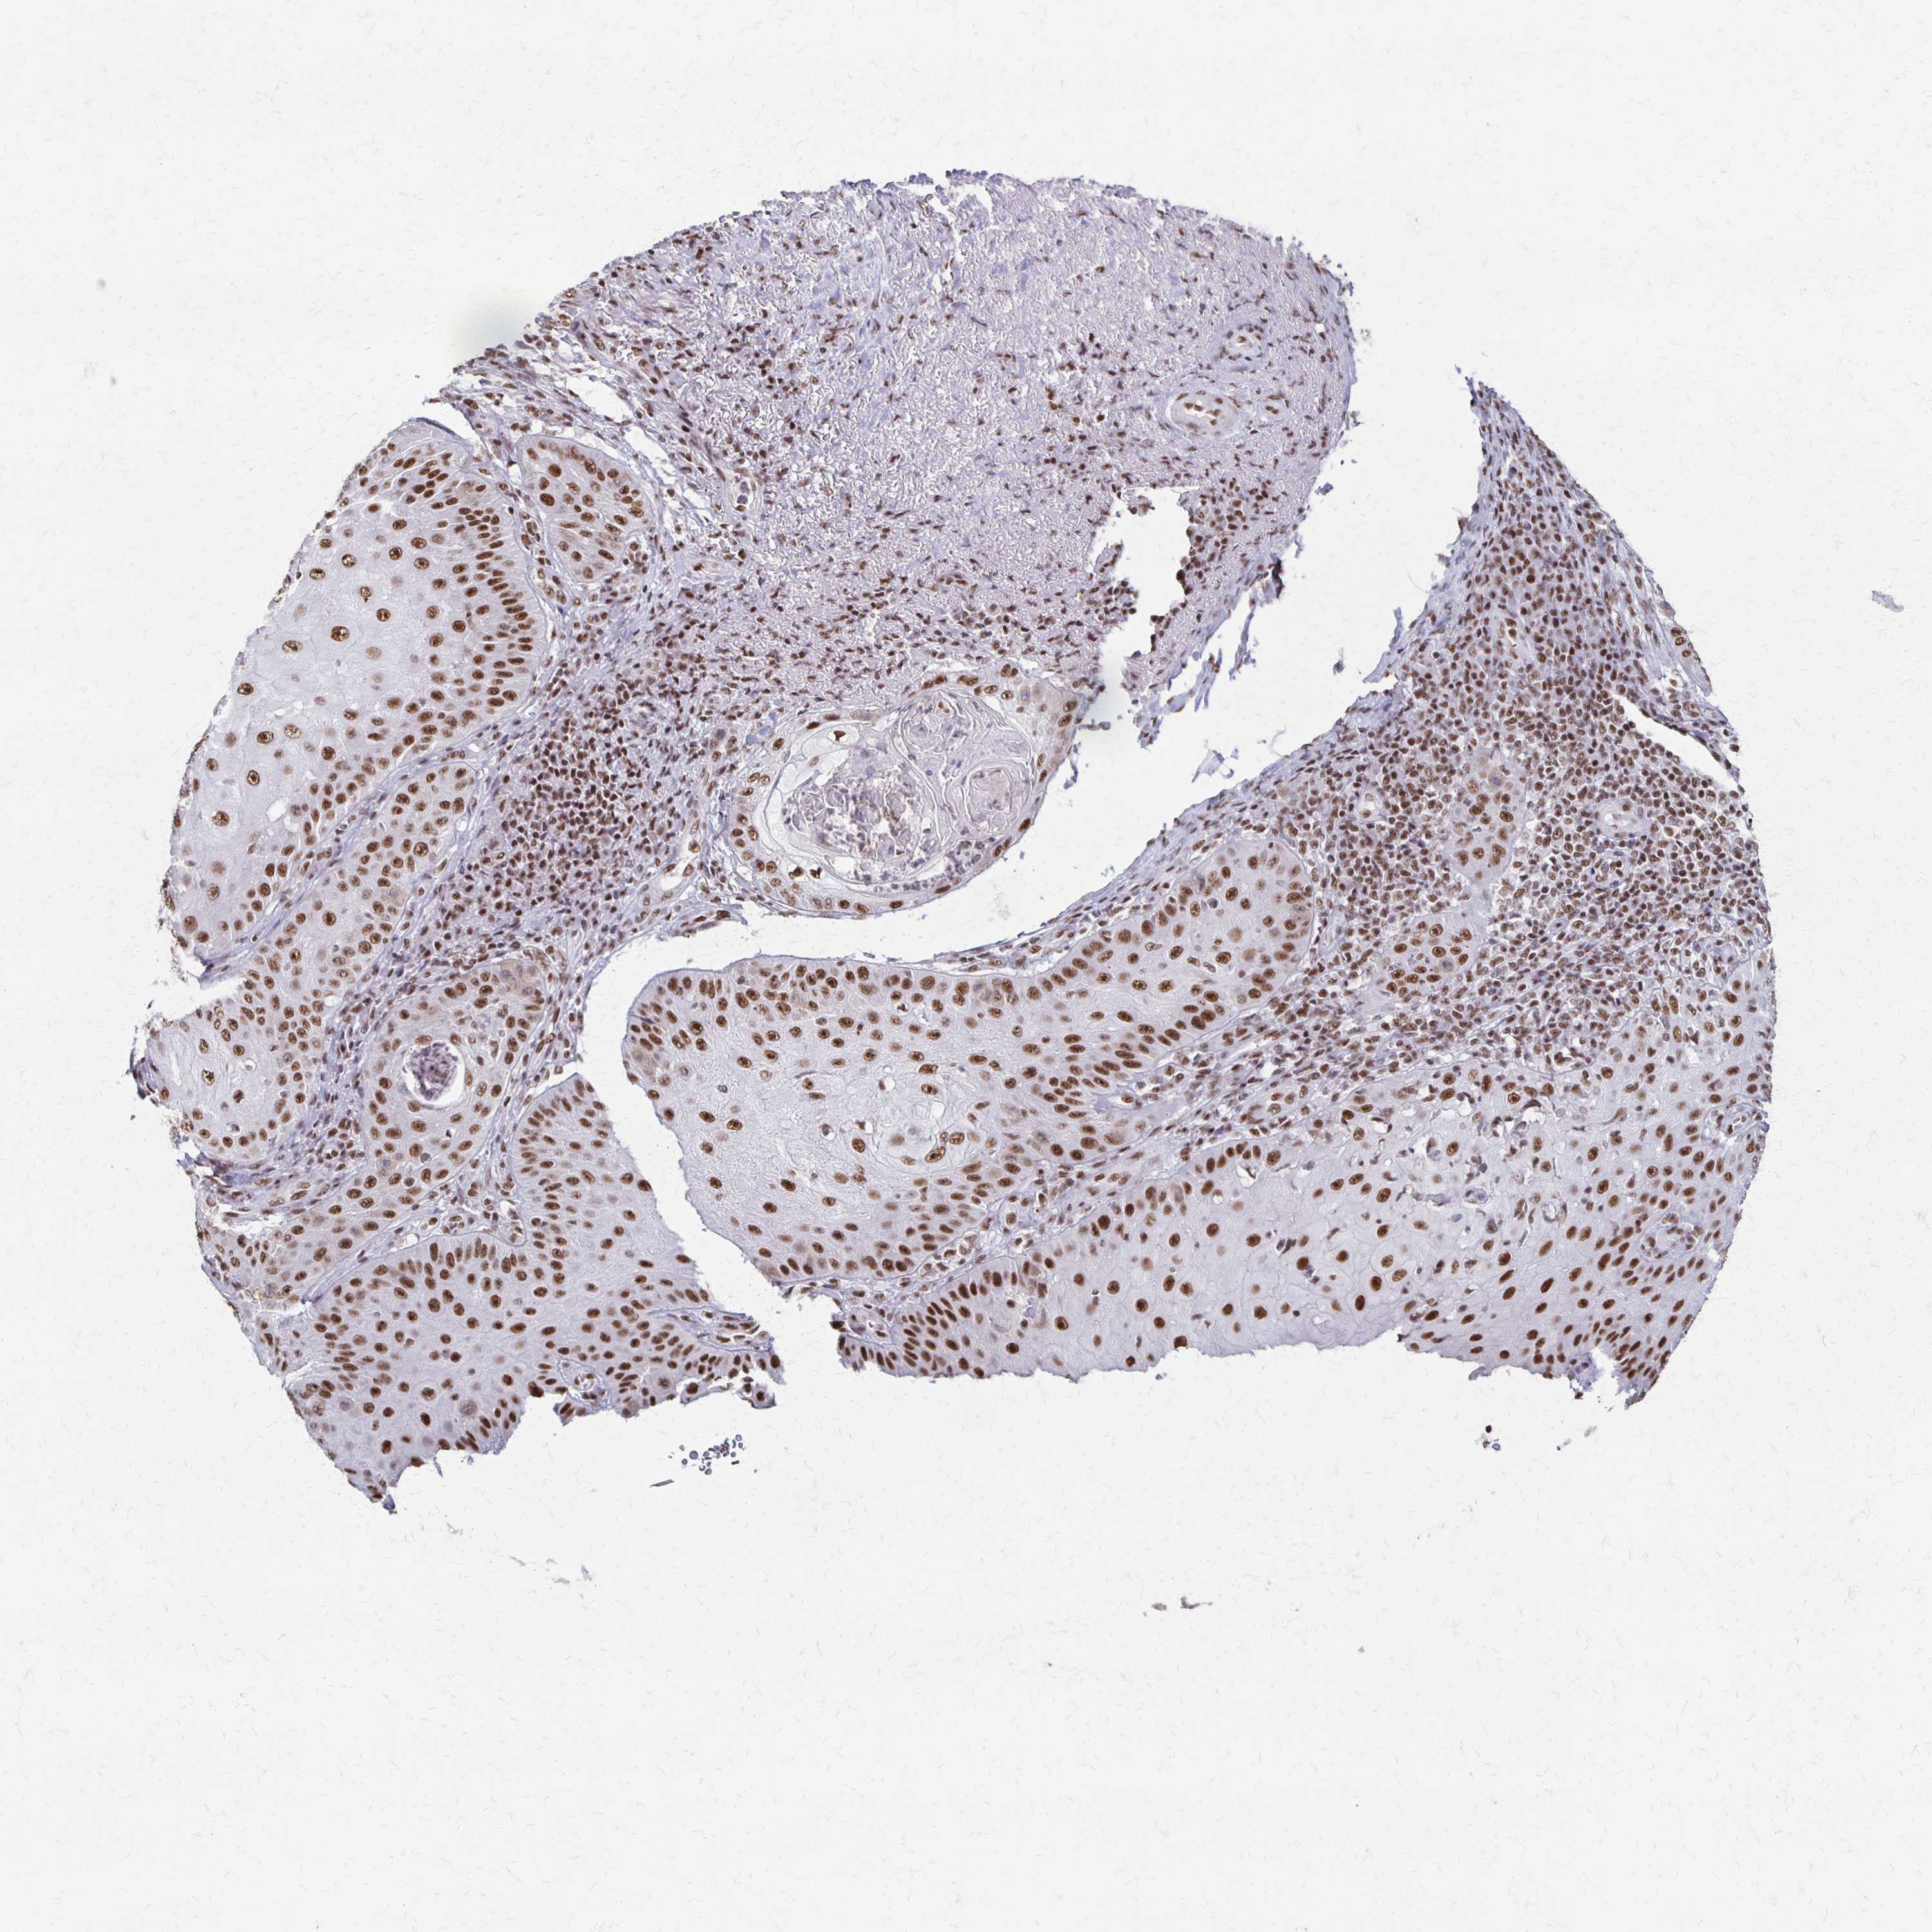

Basal cell and squamous cell cancer

SKIN CANCER - Protein expressioni

A mouse-over function shows sample information and annotation data. Click on an image to view it in a full screen mode. Samples can be filtered based on level of antibody staining by selecting one or several of the following categories: high, medium, low and not detected. The assay and annotation is described here.

Antibody stainingi

Antibody staining in the annotated cell types in the current human tissue is reported as not detected, low, medium, or high, based on conventional immunohistochemistry profiling in selected tissues. This score is based on the combination of the staining intensity and fraction of stained cells.

Each image is clickable and will lead to virtual microscopy that enables deeper exploration of all samples and also displays staining intensity scores, fraction scores and subcellular localization as well as patient and tissue information for each sample.

Staining

High

Medium

Low

Not detected

Intensity

Strong

Moderate

Weak

Negative

Quantity

>75%

75%-25%

<25%

None

Location

Nuclear

Cytoplasmic/membranous

Cytoplasmic/membranous,nuclear

Squamous cell carcinoma, NOS

Squamous cell carcinoma, metastatic, NOS

Basal cell carcinoma